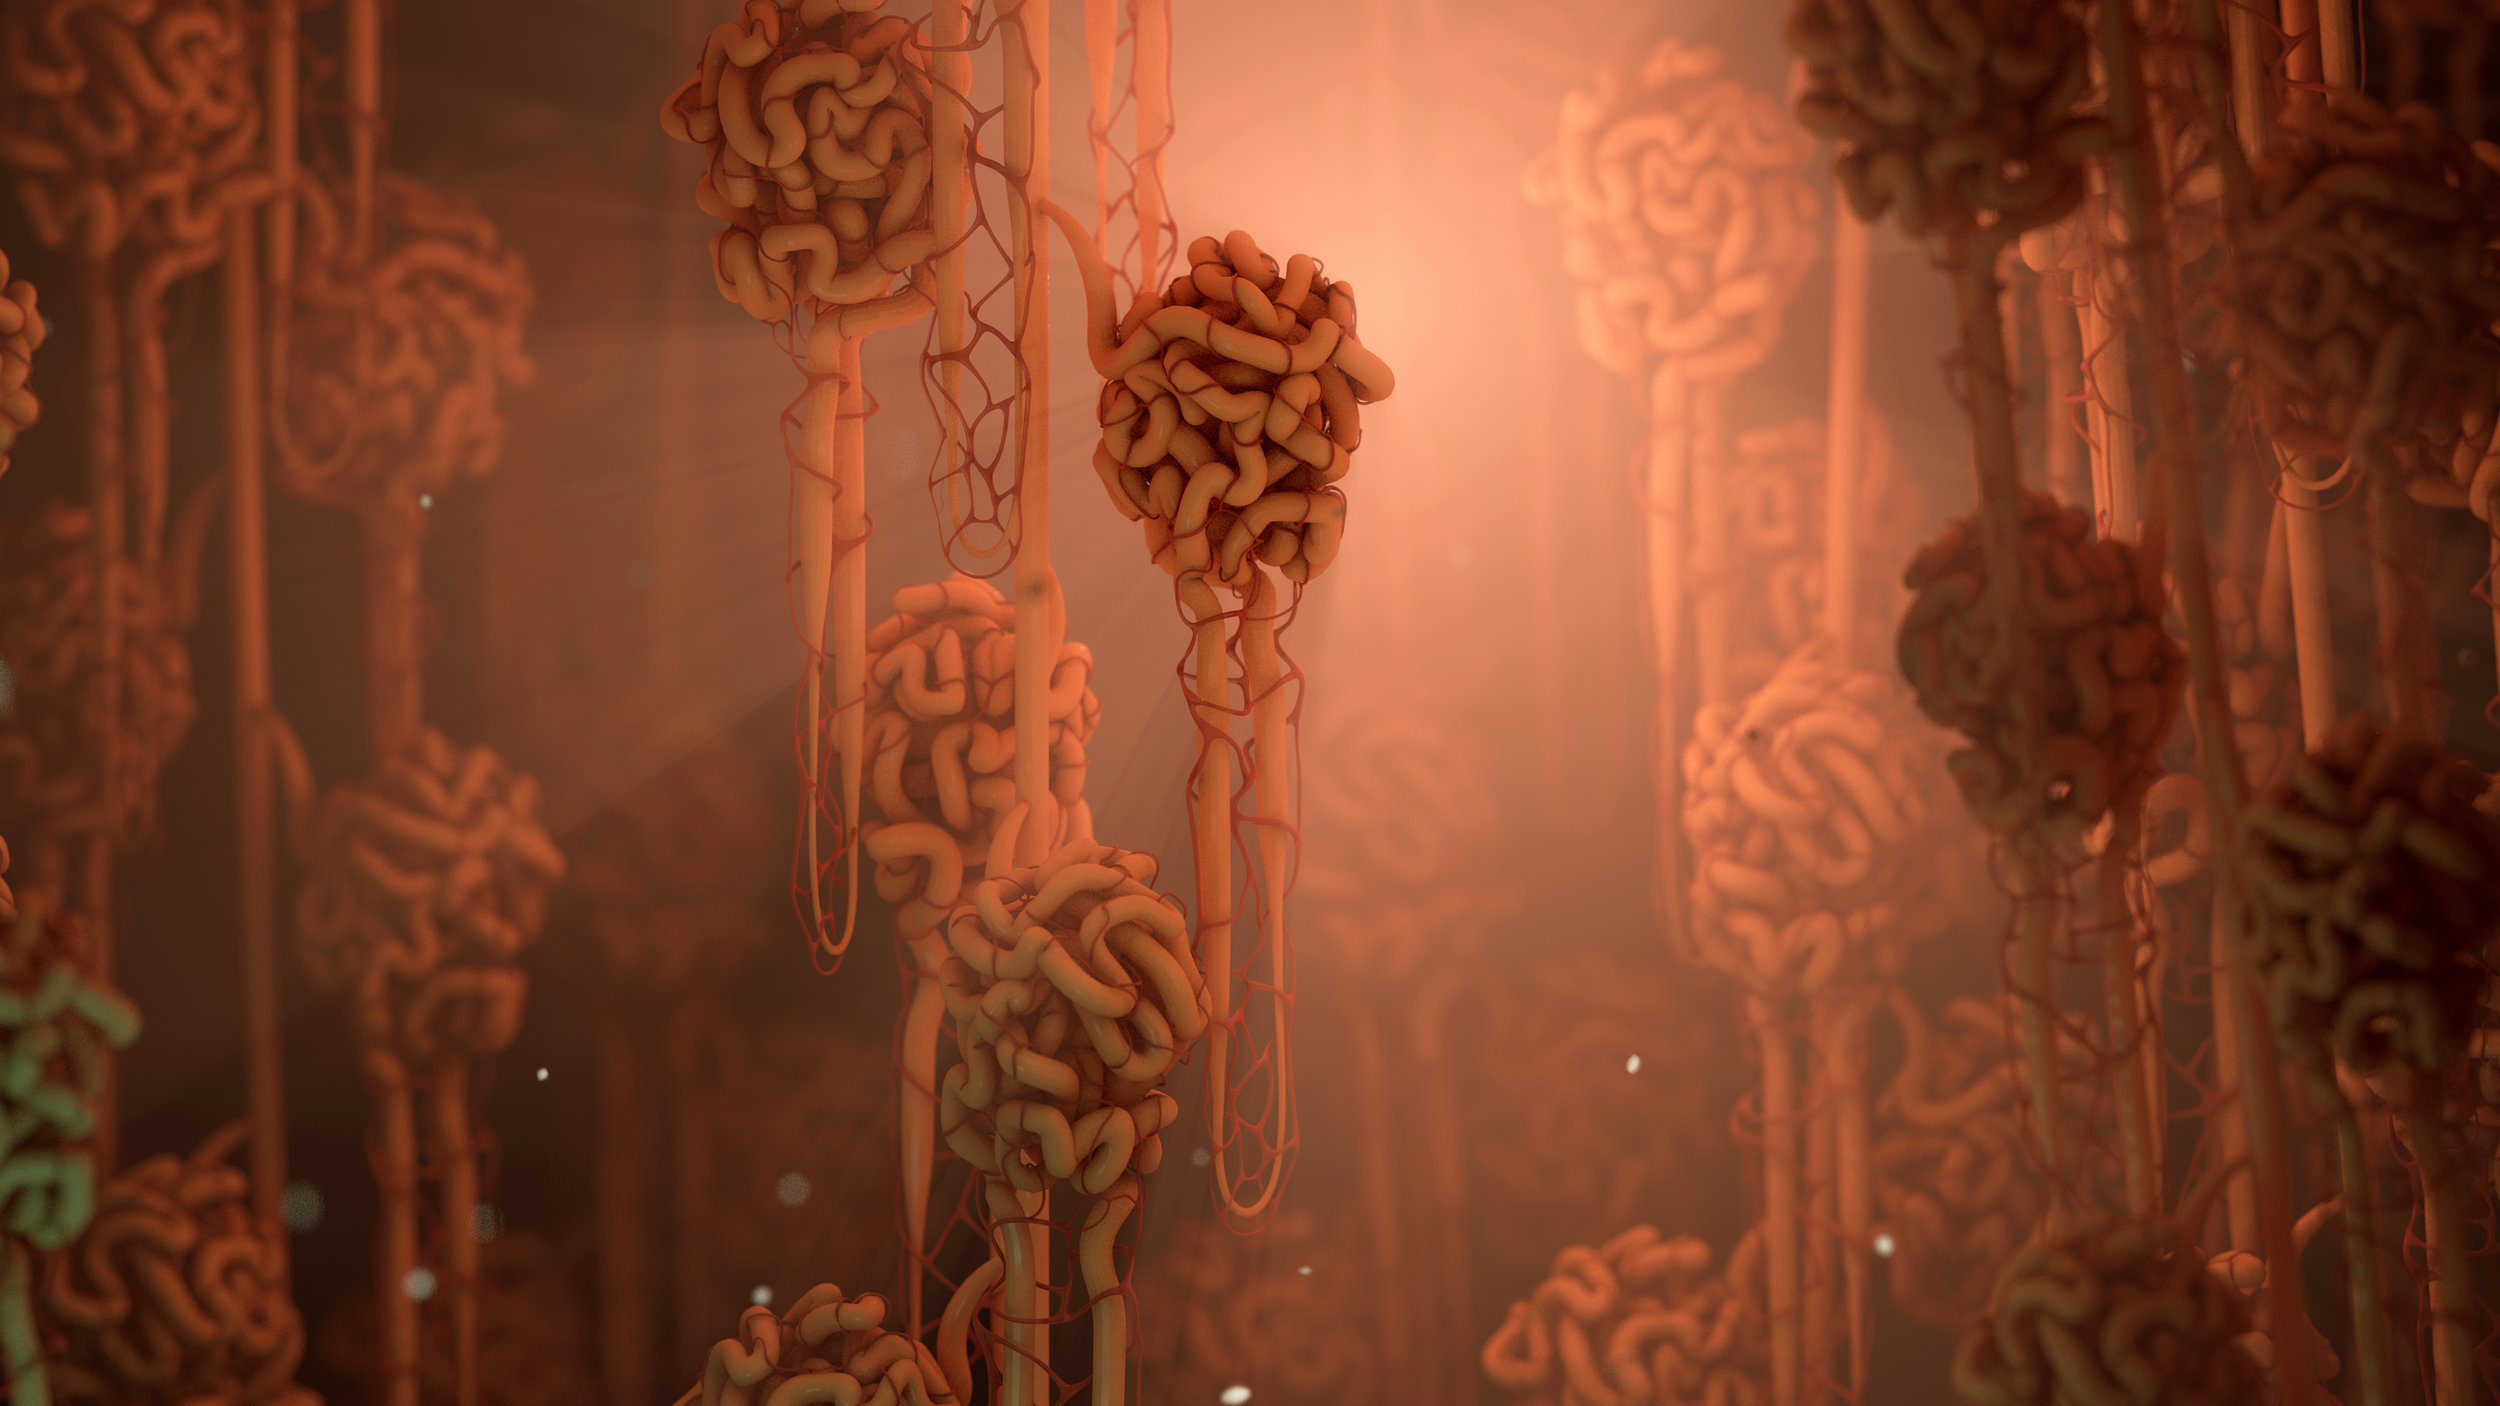

Interactive Kidneys

Rendered in WebGL